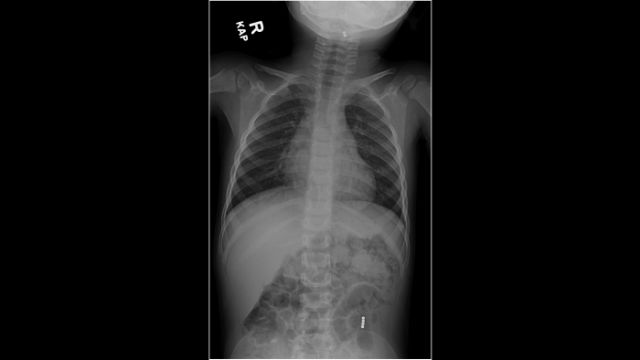

وأظهرت الأشعة السينية أن الطفل كان يحمل خرزتين مغناطيسيتين في حلقه و4 خرزات في بطنه، ولم يجد الصبي صعوبة في التنفس، لكنه كان يشعر بألم خفيف عند البلع.